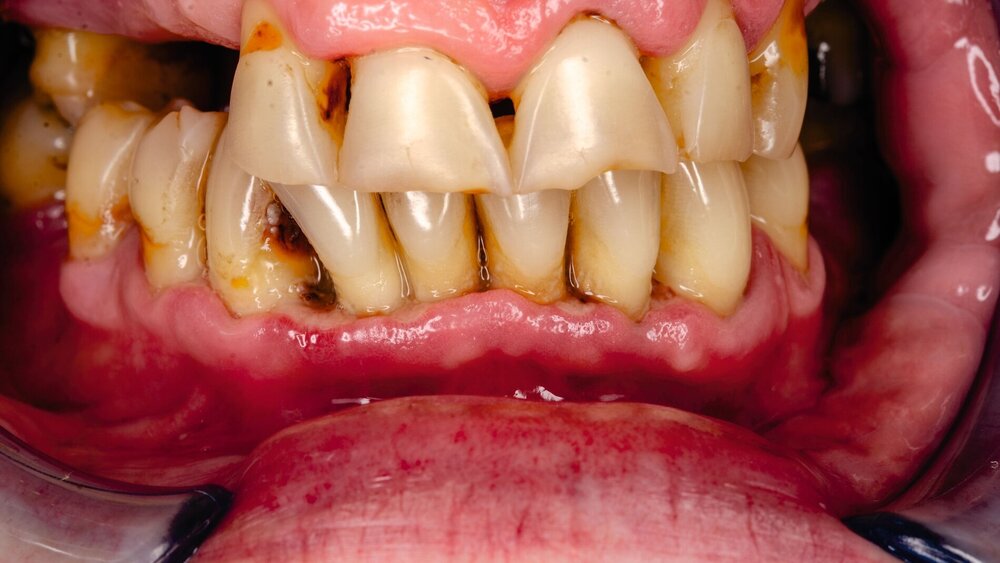

Ein Team Forschender der Hebräischen Universität Jerusalem hat diesen Mechanismus entschlüsselt und gezeigt, dass Porphyromonas gingivalis (P. gingivalis) gezielt das Immunsystem manipuliert. Als Hauptverursacher der Parodontitis kann das Bakterium langfristig das Risiko für systemische Erkrankungen wie Herz-Kreislauf-Erkrankungen, Alzheimer und Krebs erhöhen.

Die Forschenden stellten fest, dass P. gingivalis das Integrin-assoziierte Protein CD47 nutzt, um die Immunabwehr gezielt zu stören. CD47, das in Krebszellen als „Friss mich nicht“-Signal bekannt ist, schützt das Bakterium vor der Zerstörung durch Immunzellen. Zusätzlich regt P. gingivalis die Produktion von Thrombospondin-1 (TSP-1) an, einem Liganden, der die Immunaktivität weiter hemmt – insbesondere die durch Neutrophile vermittelte Bakterienbeseitigung.

„Unsere Ergebnisse deuten darauf hin, dass P. gingivalis CD47 nutzt, um Immun-Signalwege zu entführen und so die Fähigkeit des Wirts, die Infektion zu beseitigen, effektiv zu unterdrücken“, sagte Studienleiter Prof. Gabriel Nussbaum. „Dieser Mechanismus hilft zu erklären, warum dieses Bakterium in entzündlichen Umgebungen gedeiht, was zu chronischer Parodontitis führt und möglicherweise zu anderen systemischen Krankheiten beiträgt.“